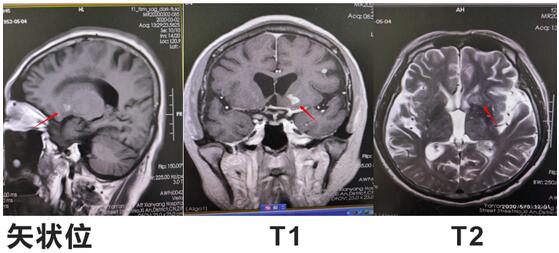

患者邱某,男,67歲 ,因“反復低熱頭痛40余天”入住我院神經(jīng)內(nèi)科三病區(qū),入院后行神經(jīng)系統(tǒng)體格檢查示:表情淡漠,腦膜刺激征陽性;行顱腦磁共振增強掃描示:顱內(nèi)可見多發(fā)點狀及小片狀結節(jié)灶,增強掃描呈小片狀及環(huán)形明顯強化,考慮①感染性病變,結核性腦膜炎可能,②轉移瘤待排:請結合臨床實驗室檢查;行腰椎穿刺術示:顱內(nèi)壓310mmH2O,潘氏試驗陽性,并于腦脊液中檢測出結核分枝桿菌(咸陽市首例)。腦脊液常規(guī):淡黃色清亮,白細胞計數(shù) 210*106/L,潘氏試驗陽性,中性粒細胞比率 90.0%。腦脊液生化:葡萄糖 1.40mmoI/L,氯 105.5mmol/L,微量總蛋白 2749mg/L,陳萍主任醫(yī)師、代昌飛副主任醫(yī)師及科室其他醫(yī)師慎重討論后考慮:結核性腦膜炎,并立即制定抗結核、降低顱內(nèi)壓、抑制腦水腫、減輕炎癥反應等相關治療方案。王寶艷護士長指導護理應加強護理,早期康復。經(jīng)討論匯總,為該患者制定特色治療方案,動態(tài)調(diào)整,密切觀察。在科室醫(yī)生護士的精誠協(xié)作下,患者渡過險關。復查腰椎穿刺術:初壓:170mmH20,常規(guī):潘氏試驗陽性;白細胞計數(shù) 120*106/L。淋巴細胞百分率 10.0%,中性粒細胞百分率 90.0%。生化:微量總蛋白 1503mg/L。出院后繼續(xù)抗結核治療。